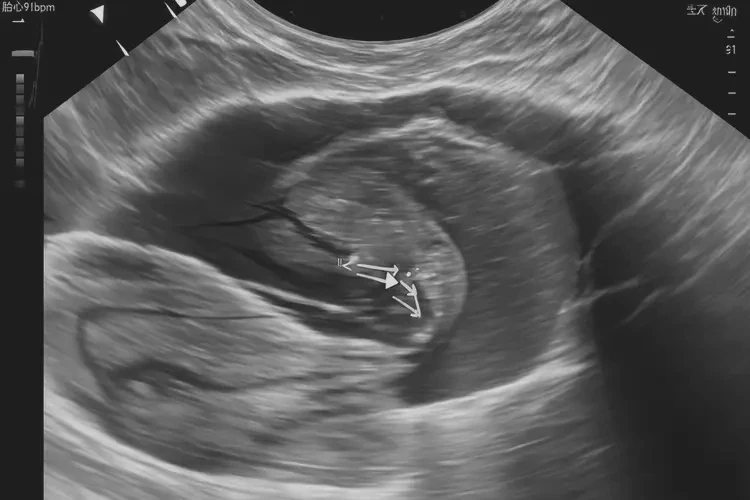

胎心率91次/分钟在孕13周3天可能存在风险

胎心率是评估胎儿健康状况的重要指标之一。在孕13周3天时,正常的胎心率范围通常在110-160次/分钟之间。胎心率低于110次/分钟可能表明胎儿存在缺氧或其他健康问题。胎心率91次/分钟低于正常范围,可能存在一定的风险,需要引起重视并及时咨询医生。